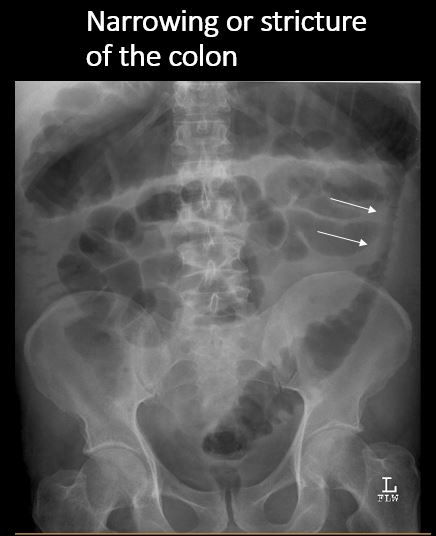

There is narrowing or stricture involving the stomach or bowel. [Yes/No]